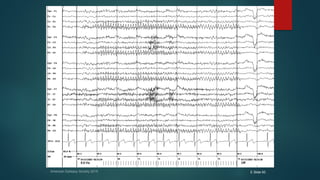

๏ต Normal burst of theta in the EEG of an adult during

drowsiness

๏ต Note the prominent intermixed beta activity

๏ต and electrode artifact at F7 and F3 that combine to

make the appearance โ€œspikier.โ€

Normal โ€œsuspiciousโ€ EEG

๏ต Many normal variants and variations of normal EEG have

a predilection for the temporal lobe and mimic

epileptiform discharges.